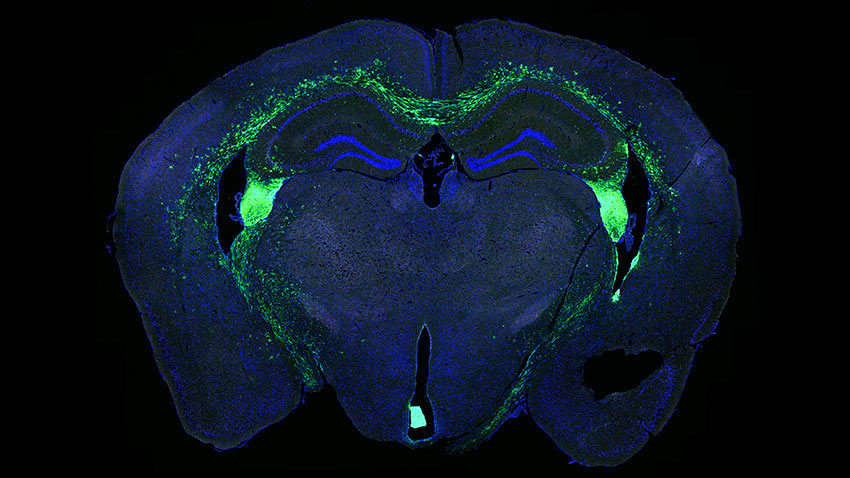

当给予一种新的单克隆抗体治疗时,人神经干细胞移植(绿色)存活并在小鼠大脑(蓝色)中迁移。 密歇根医学院的一项研究表明,一种新的干细胞治疗方法使用抗体代替传统的免疫抑制剂药物,可以有效地保存小鼠大脑中的细胞,并有可能快速进行人体试验。

在这项研究中,研究人员使用单克隆抗体抑制小鼠的免疫系统,并将结果与传统的免疫抑制药物他克莫司和霉酚酸酯进行比较。他们使用荧光素酶(一种使萤火虫发光的蛋白质)追踪植入的人类神经干细胞的存活情况。